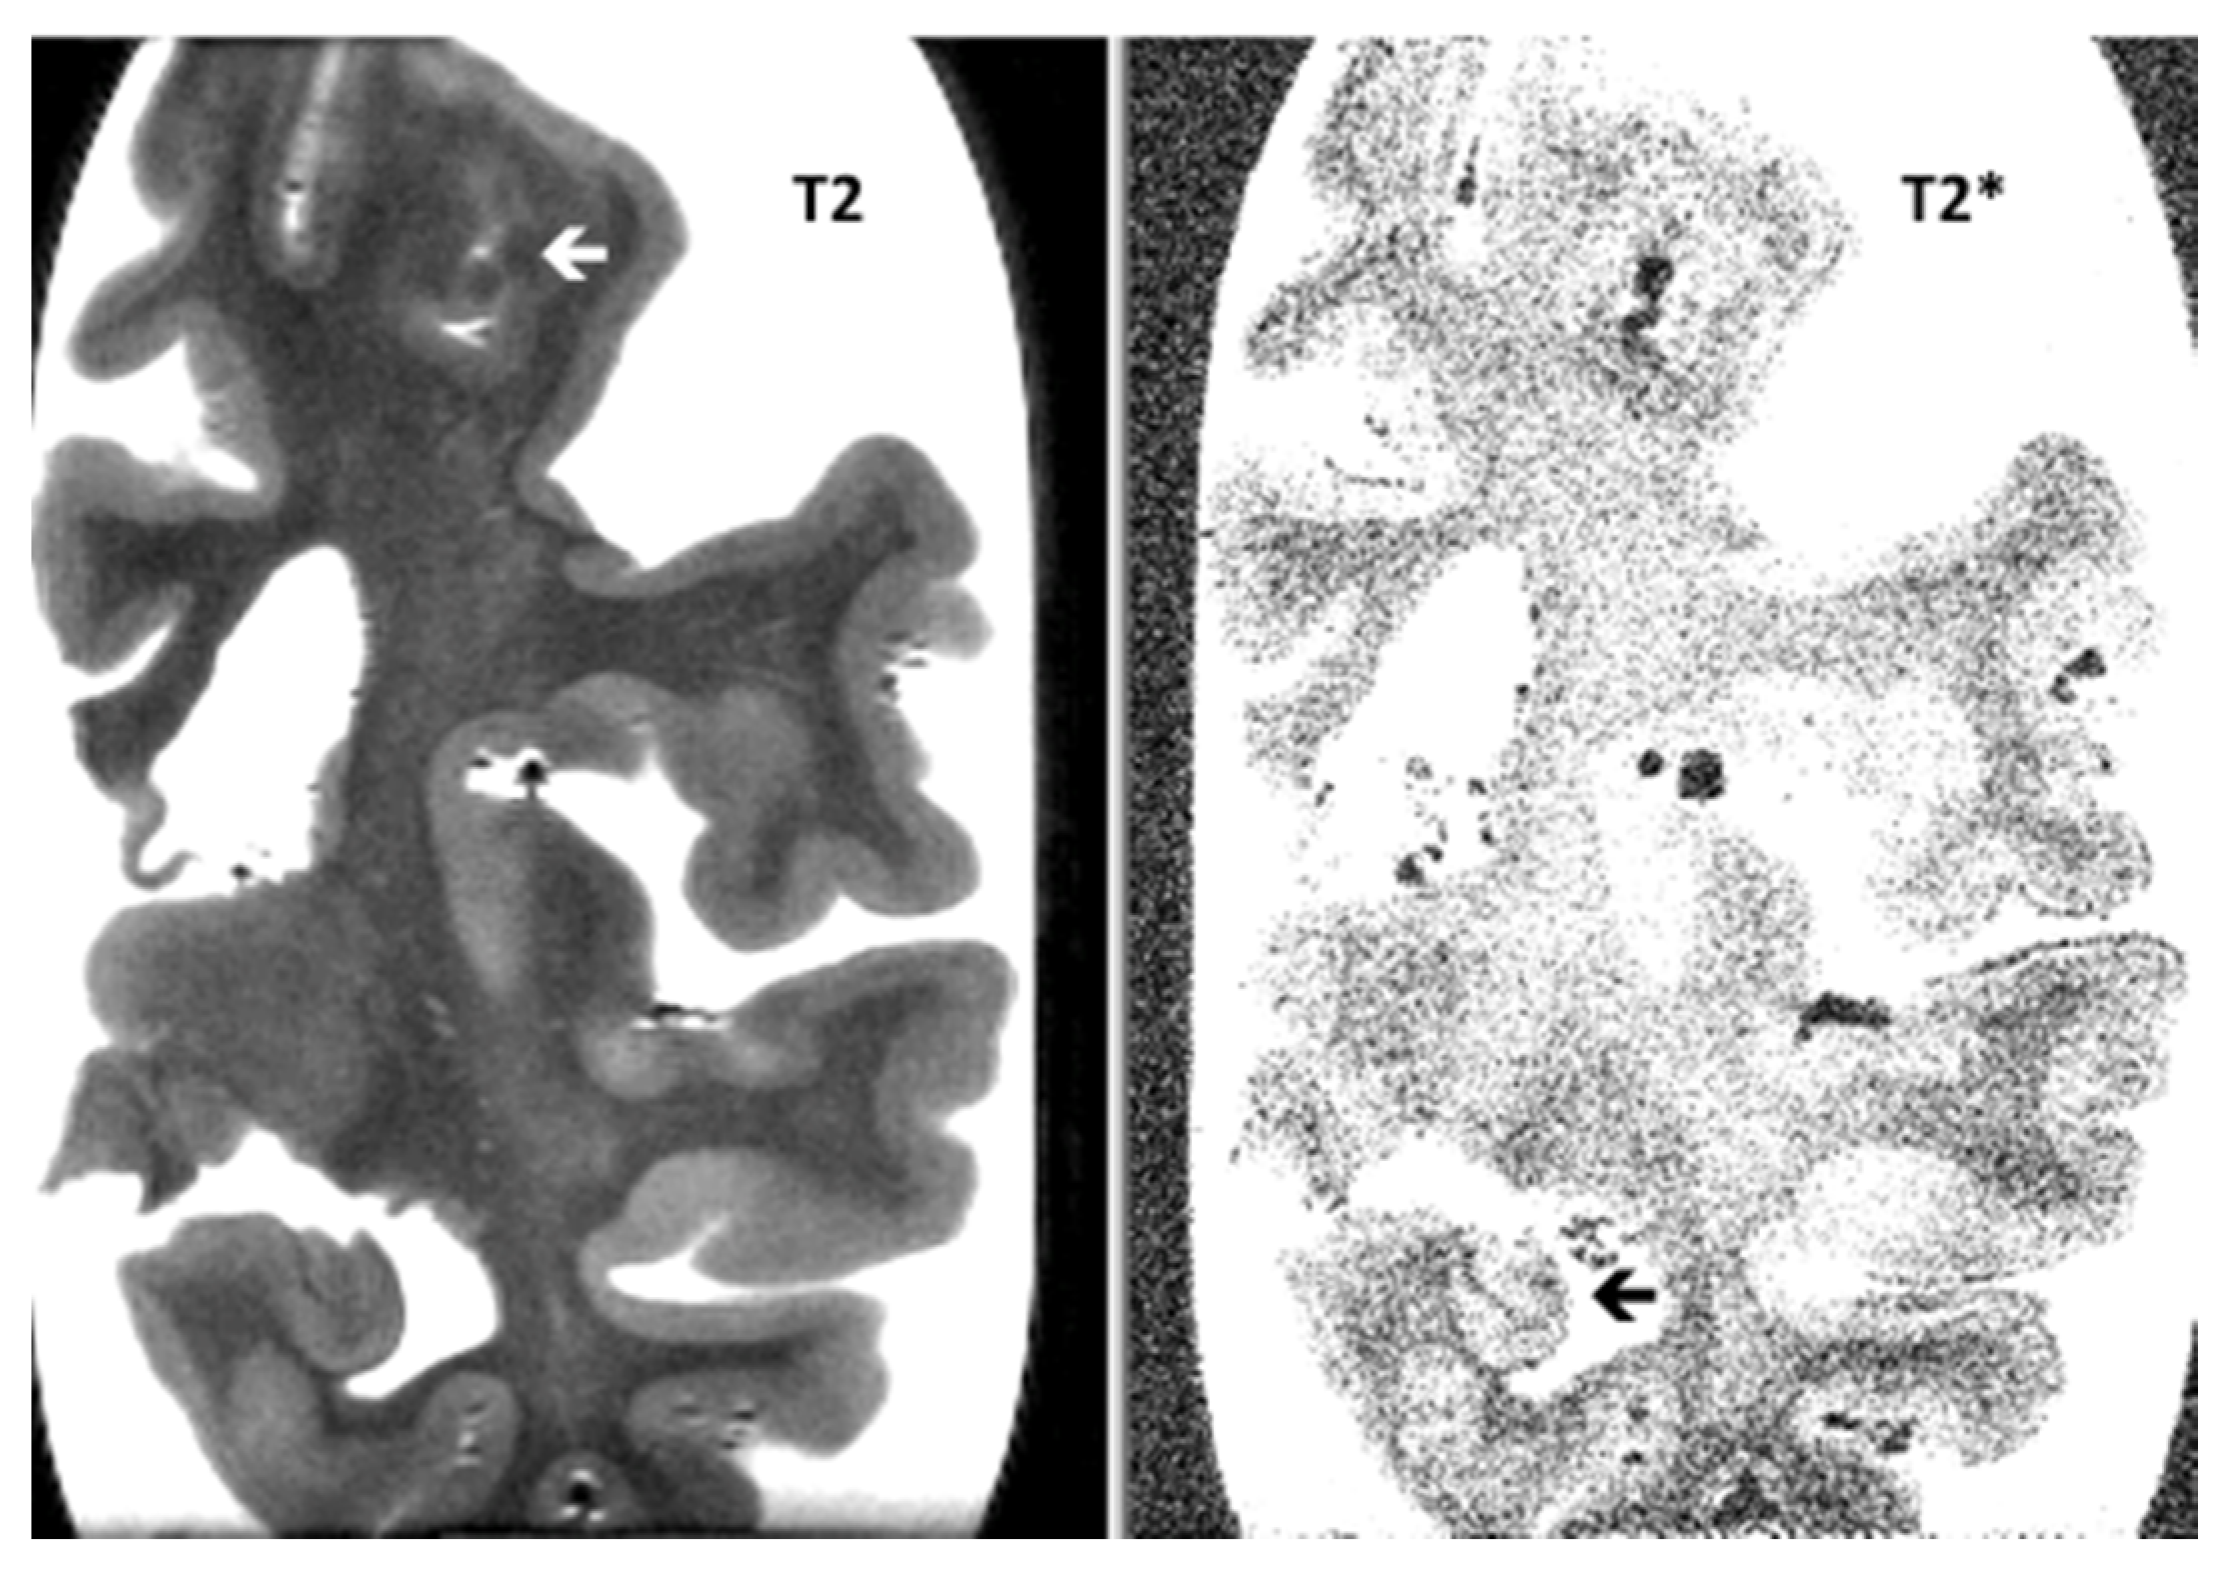

Post-Mortem 7.0-Tesla Magnetic Resonance Imaging of the Hippocampus in Progressive Supranuclear Palsy with and without Cerebral Amyloid Angiopathy

De Reuck, J.; Auger, F.; Durieux, N.; Maurage, C.-A.; Deramecourt, V.; Cordonnier, C.; Pasquier, F.; Leys, D.; Bordet, R. Post-Mortem 7.0-Tesla Magnetic Resonance Imaging of the Hippocampus in Progressive Supranuclear Palsy with and without Cerebral Amyloid Angiopathy. NeuroSci 2020, 1, 115-120. https://doi.org/10.3390/neurosci1020011